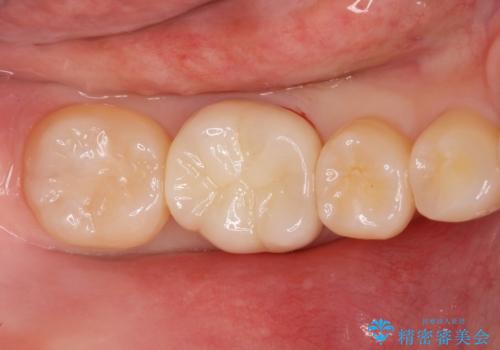

古い樹脂と虫歯を拡大鏡下でしっかり取り除き、ジルコニアクラウンにて治療しました。

ジルコニアクラウンは劣化しにくく虫歯の再発のリスクが低いです。

白い被せ物が入りとても満足して頂けました。